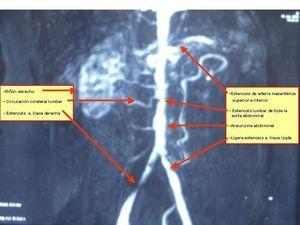

Debido a los hallazgos radiológicos de aneurisma y asimetría renal leve, solicitamos una angio-TC torácica en la que se evidencia un aneurisma de aorta descendente distal, de tipo sacular, de 4,3 cm de diámetro. Ampliamos estudio con una angio-IRM toráco-abdominal (figura 2, figura 3, figura 4, figura 5) en la que se observan signos de miocarditis. Estenosis en múltiples niveles de la aorta, con signos de inflamación activa y aneurisma focal de aorta torácica descendente. Afectación difusa de aorta abdominal, así como de sus principales ramas viscerales. Triple arteria renal derecha y doble arteria renal izquierda. Estenosis de la arteria polar superior izquierda.

Figura 4. Angio-IRM abdominal.